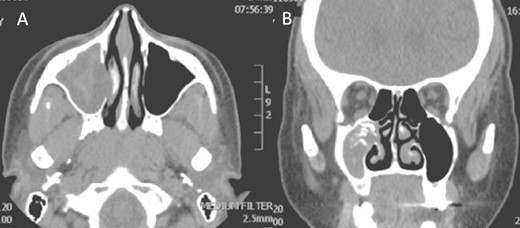

Isolated maxillary fungal ball

A 30-year-old lady presented to the clinic with a complaint of right facial pain, recurrent rhinorrhea with post-nasal discharge, nasal endoscopic examination was unremarkable. A non-contrast computed-tomography scan (NCCT) of the paranasal sinuses (Fig. 1) was suggestive of isolated right fungal maxillary fungal ball (FB). The patient underwent endoscopic sinus surgery (ESS) with (Fig. 2) right middle meatal antrostomy and removal of fungal debris. The patient was followed up regularly and remained symptom free.

Axial (A) and coronal (B) images of a nonenhanced CT scan of the paranasal sinuses showing right maxillary sinus complete heterogenous opacification.